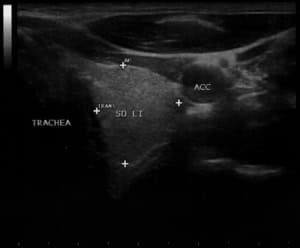

U.a. weisen Gewichtsveränderungen, Zyklusunregelmäßigkeiten und emotionale Instabilität auf Schilddrüsenfunktionsstörungen hin. Derbe Veränderungen in der Schilddrüse hingegen sind verdächtiger als weiche. Zu jeder Schilddrüsenuntersuchung gehört auch der Ultraschall von Schilddrüse und Halsweichteilen (Schilddrüsensonographie). Hierdurch lassen sich Größe und evtl. Veränderungen erkennen sowie relevante Strukturen in der vorderen Halsregion mit beurteilen, insbesondere Nebenschilddrüsen und Lymphknoten. Anhand des Schallmusters und des Durchblutungsmusters (Perfusion) lassen sich häufig bereits Krankheitsbilder festmachen.

So findet sich bei einer Autoimmunhyperthyreose (M. Basedow), einer zumeist schweren Form einer Schilddrüsenüberfunktion, eine ausgeprägte Echoarmut in Verbindung mit einer stark vermehrten Durchblutung des Schilddrüsengewebes. Von den Knoten verdienen solche mit Mikroverkalkungen und einer vermehrten Binnenperfusion verstärkte Aufmerksamkeit.

Kalte Knoten sind insbesondere bei auffälligem Tastbefund und Schallmuster hinsichtlich ihrer Dignität weiter abzuklären. Hierzu kann – ggf. auch Ultraschall-kontrolliert – der Befund punktiert werden (Schilddrüsenpunktion, Feinnadelpunktion). Ebenso können schmerzhafte Einblutungen in die Schilddrüse mittels einer Punktion entlastet und so fast unmittelbar Beschwerdefreiheit erreicht werden.